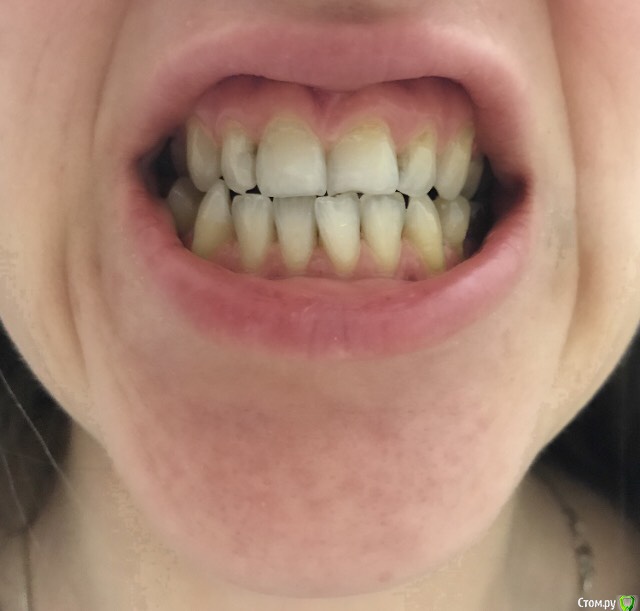

Решилась на исправление прикуса. Была консультация с ортодонтом 15 лет назад, рекомендовали операцию.

Сейчас на паре консультаций противоречивые и неуверенные ответы, может помогут брекеты, может нет.

Хочу понимать нужна ли ЧЛХ. Может сейчас системы позволят сделать прикус правильным без хирургии.

Верхних 8к нет, нижние стоят

6го нижнего нет с 10 лет, в последствии планируется имплантация.